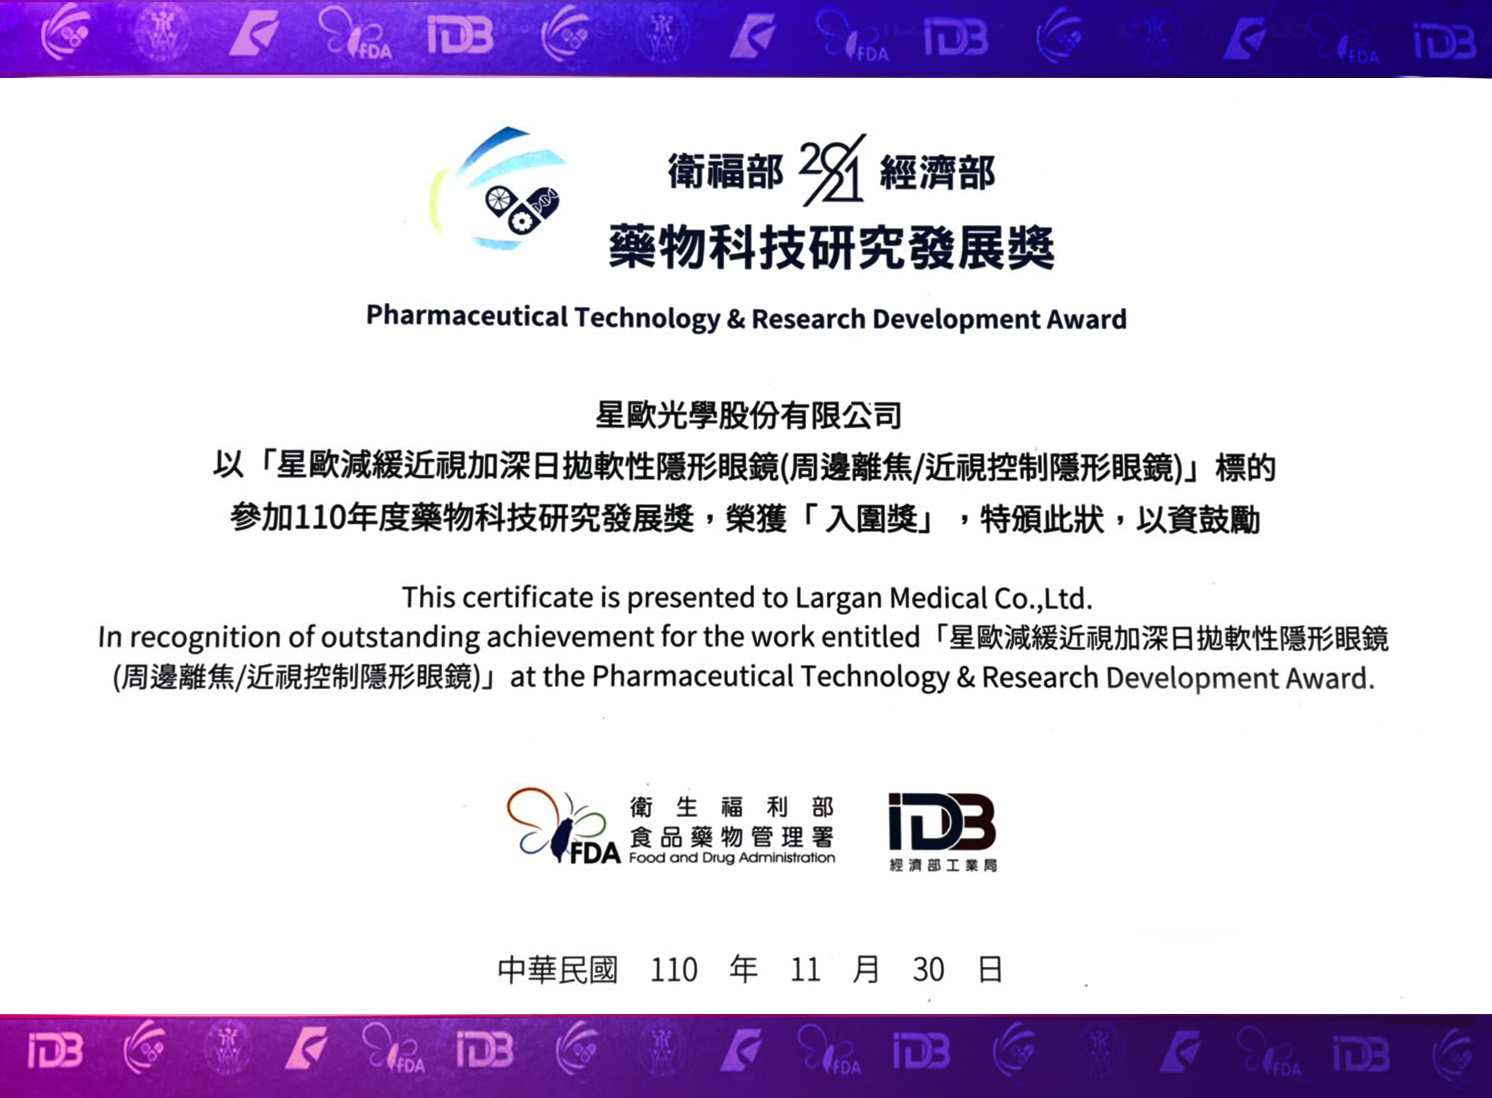

专业研发团队

20年丰富的

研发及生产经验

研发及生产经验

超高性价比